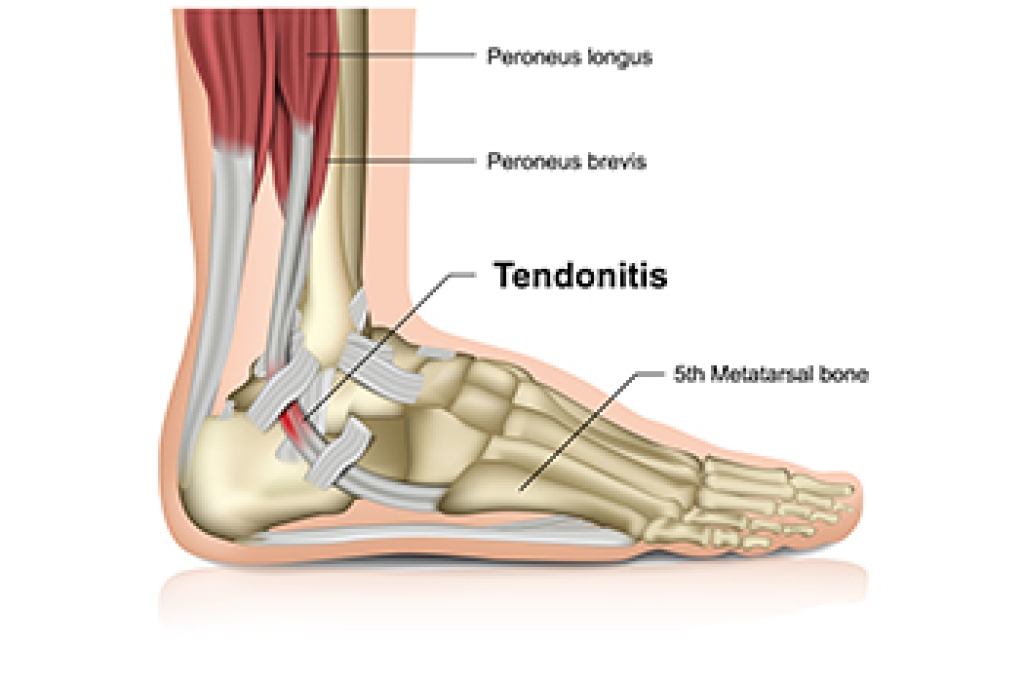

Achilles Tendon Injury in Dancers

Dancers place significant strain on the Achilles tendon due to repetitive movements, jumps, and intense footwork. This can lead to inflammation, microtears, or even more severe injuries if not properly managed. Overuse, inadequate warm-ups, and wearing improper footwear increase the risk of injury. Strengthening the calf muscles and improving flexibility through targeted exercises can help reduce strain on the tendon. Proper technique, gradual intensity progression, and sufficient rest between training sessions are essential for injury prevention. Supportive footwear and using appropriate dance surfaces can also minimize stress on the Achilles tendon. Paying attention to early signs of discomfort, such as stiffness or pain, allows for timely intervention. If you have sustained an Achilles tendon injury from dancing, it is suggested that you promptly contact a podiatrist who can offer effective treatment solutions and prevention tips.

What Is the Achilles Tendon?

The Achilles tendon is a tendon that connects the lower leg muscles and calf to the heel of the foot. It is the strongest tendon in the human body and is essential for making movement possible. Because this tendon is such an integral part of the body, any injuries to it can create immense difficulties and should immediately be presented to a doctor.

What Are the Symptoms of an Achilles Tendon Injury?

There are various types of injuries that can affect the Achilles tendon. The two most common injuries are Achilles tendinitis and ruptures of the tendon.

Achilles Tendinitis Symptoms

- Inflammation

- Dull to severe pain

- Increased blood flow to the tendon

- Thickening of the tendon

Rupture Symptoms

- Extreme pain and swelling in the foot

- Total immobility

Treatment and Prevention

Achilles tendon injuries are diagnosed by a thorough physical evaluation, which can include an MRI. Treatment involves rest, physical therapy, and in some cases, surgery. However, various preventative measures can be taken to avoid these injuries, such as:

- Thorough stretching of the tendon before and after exercise

- Strengthening exercises like calf raises, squats, leg curls, leg extensions, leg raises, lunges, and leg presses